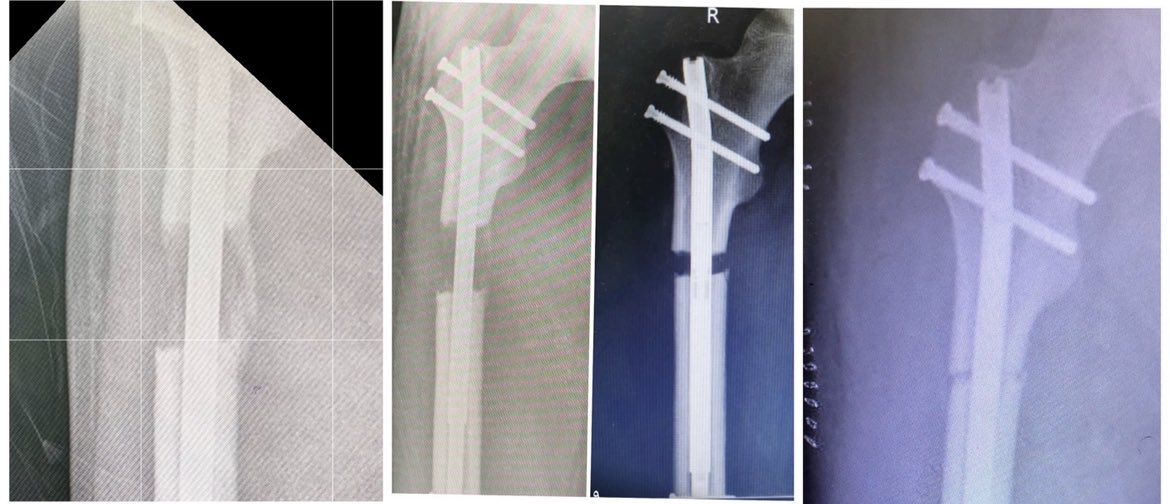

🔹يتم التطويل عن طريق عده اجهزه:

خارجيه/ والاشهر جهاز اليزاروف او الجهاز الحيزي الحلقي TSF او الاجهزه الجانبيه كجهاز اورثوفكس

داخليه/ كالمسامير النخاعيه المغناطيسيه واشهرها precice ولها ريموت خارجي للتطويل